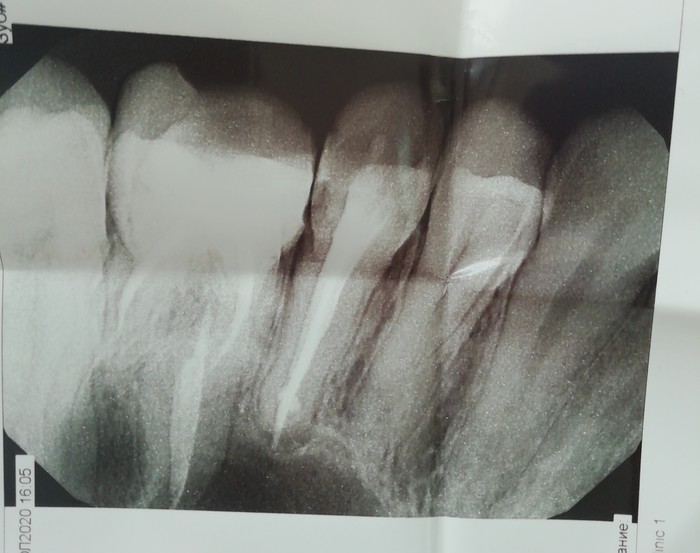

Доброго времени суток. Ближе к делу. Рентген верхнего пятого (с пломбой).

На пятый день (вчера) я снова сходила в бесплатную стомотогию, тот же врач сказал что может быть киста, придется удалять зуб.. Я такая угу, понятно, приплыли. Говорит делай рентген в платной клинике, а то у нас на днях сломался. Результат вы видите выше. Там же

меня проконсультировал другой врач. Цитирую ее "приговор": пульпопериодонтит, Воспаление за верхушкой над небным конем.

Экстракцию пульпы, ультразвуковая чистка.

Обратно приехала в бесплатную, показала, сказала что да, нервы надо удалять, а у нас нет возможности это сделать, нужно в платной. Чем быстрее тем лучше, а то другие зубы тоже пострадают.

Самое главное: с 4 дня температура держится 37- 37,5 и не спадает. Боль постоянная, ноющая, на постукивание по зубу реагирую сильной болью. Десна все так же воспалены. Холодное пить не могу, горячее более менее, есть могу только с левой стороны.

Как думаете что с зубом, как поступить? В платной выставили цену 11к, для студентки больше деньги.